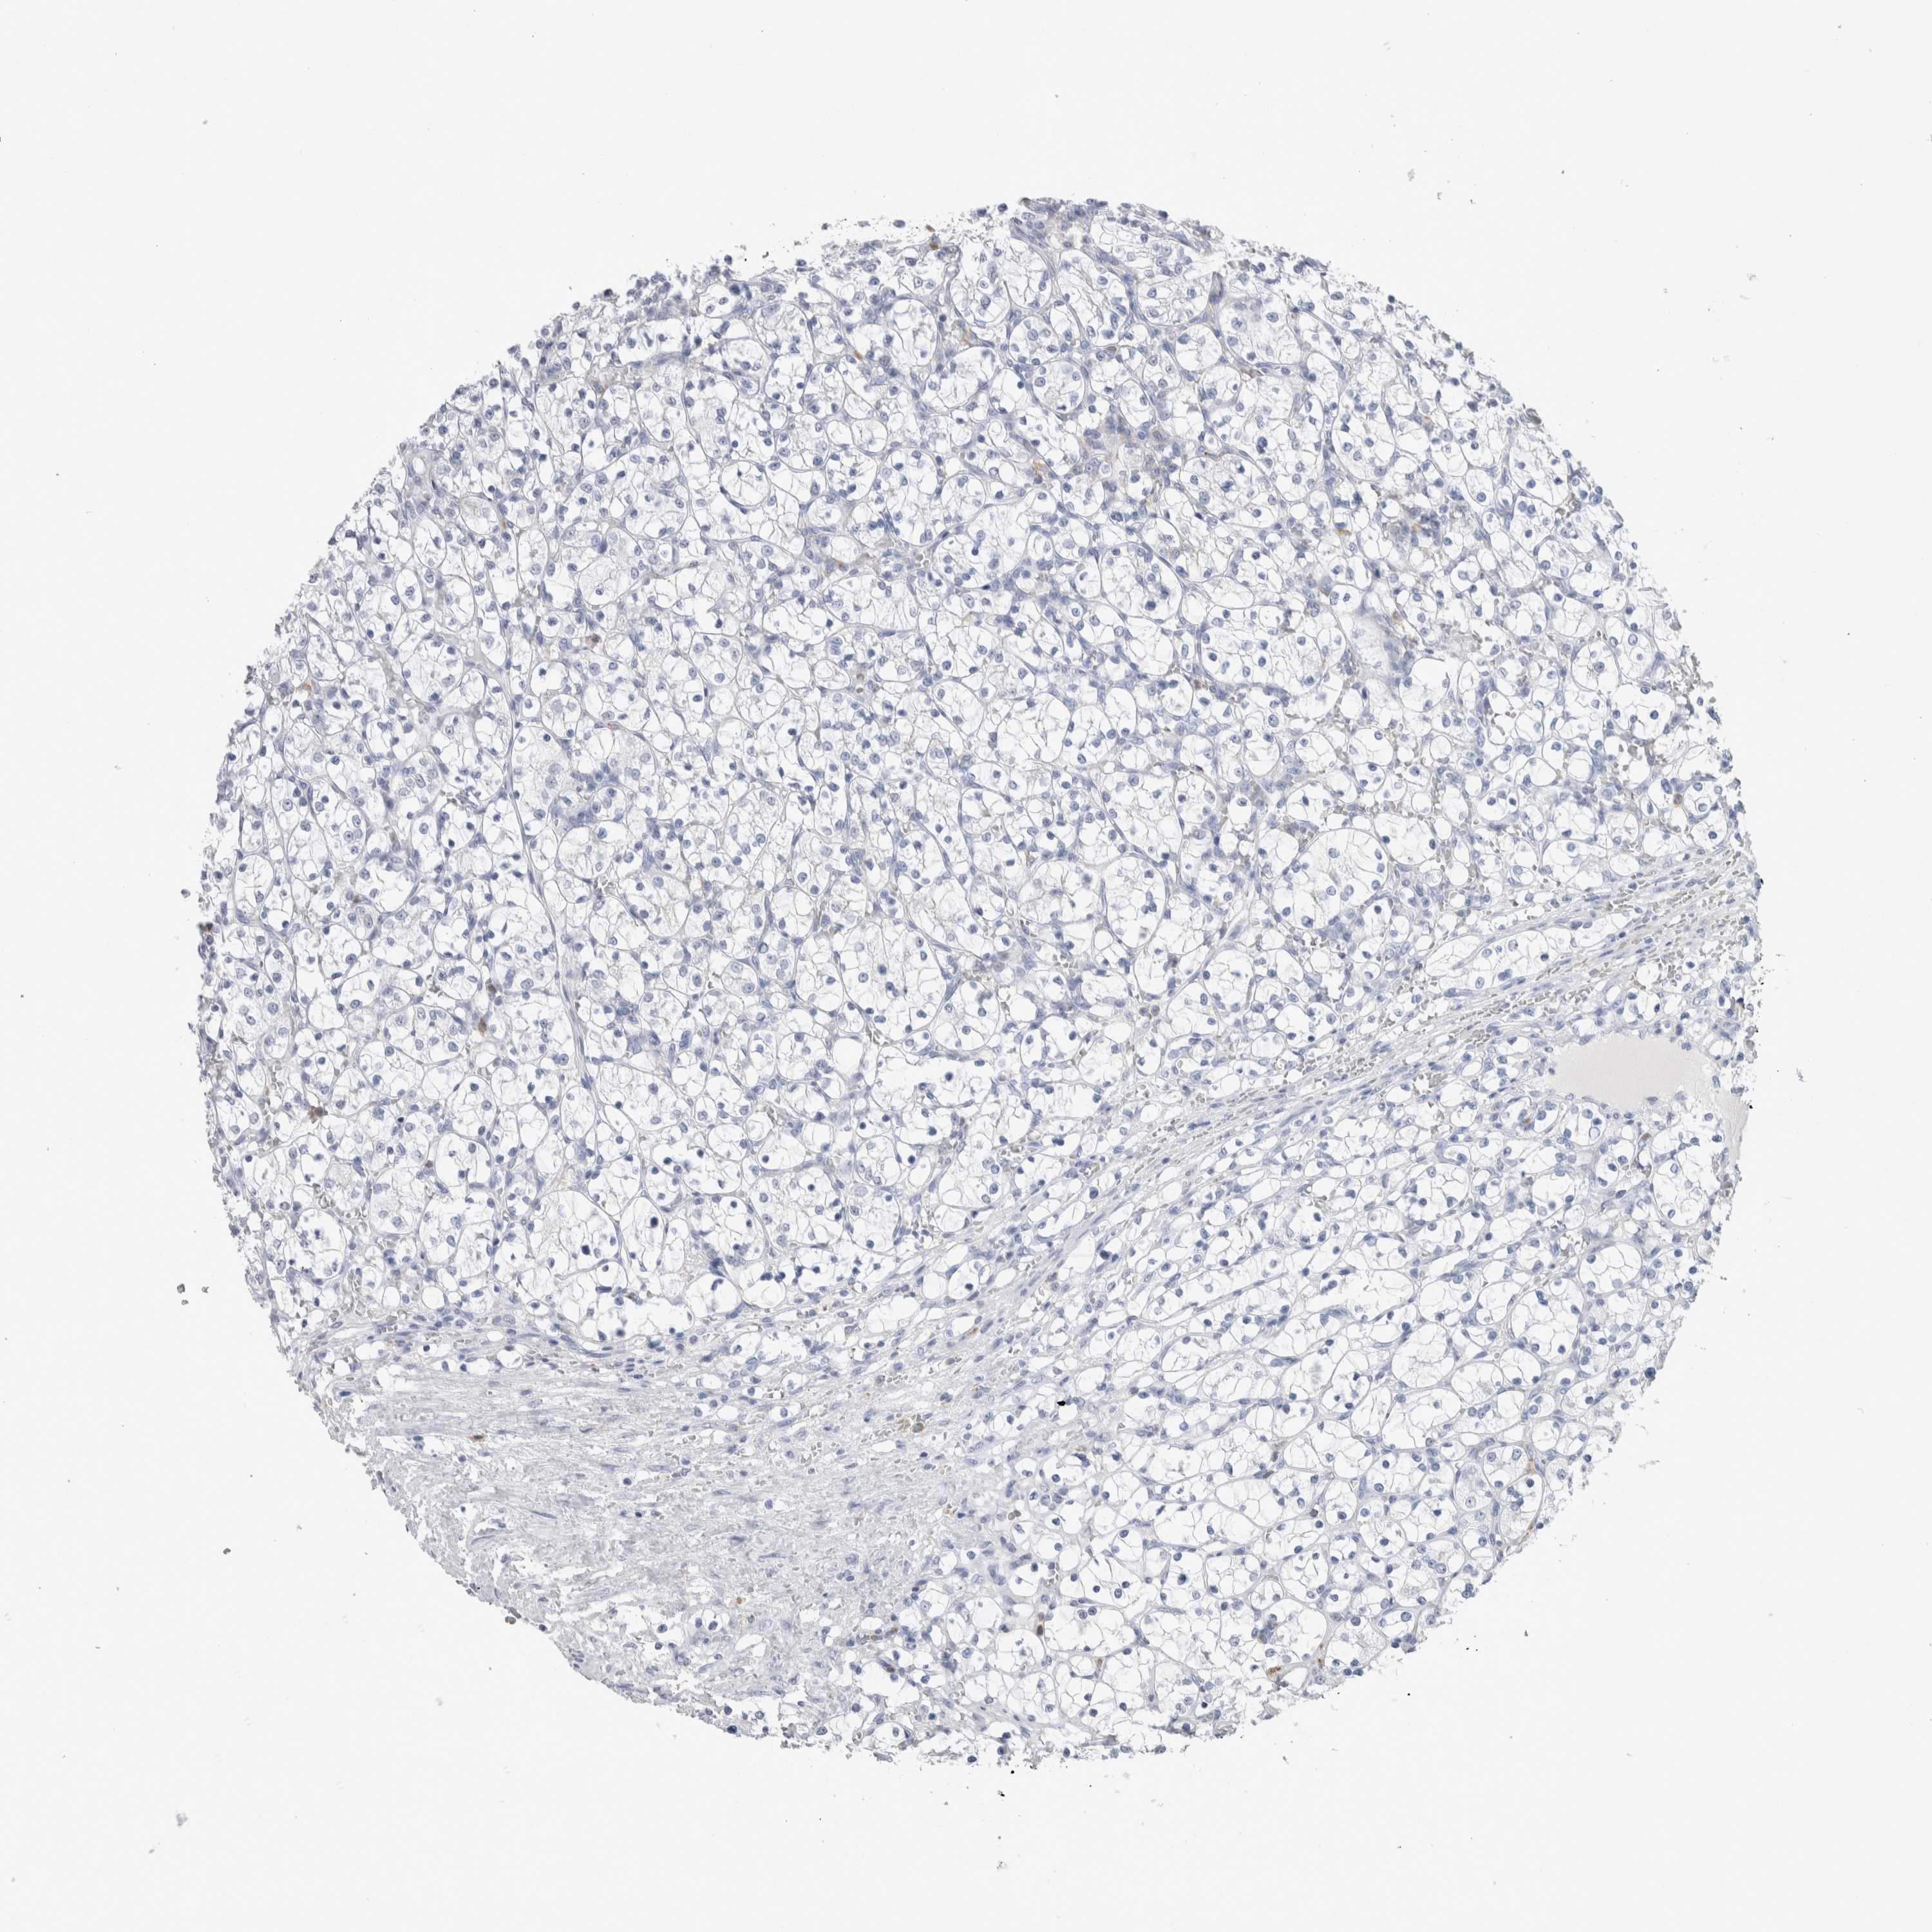

KIDNEY RENAL CLEAR CELL CARCINOMA (TCGA) - Interactive survival scatter ploti

LURAP1L is validated prognostic, high expression is favorable in Kidney Renal Clear Cell Carcinoma (TCGA)

: 6.11

Average pTPM 10.2

Number of samples 521